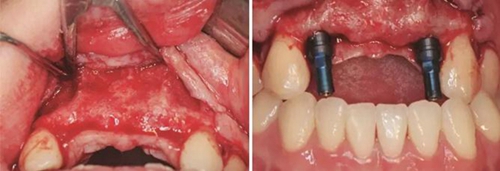

圖17 CBCT測量骨量變化 圖18 早期修復(fù)戴牙當(dāng)天

(4)2015年3月—2015年12月:早期修復(fù)伴軟組織誘導(dǎo)成形對(duì)患者制取開窗印模后,使用橋用金屬臨時(shí)基臺(tái),制作聚甲基丙烯酸甲酯(PMMA,登士柏公司,德國)經(jīng)CAD/CAM切削的臨時(shí)修復(fù)橋體,戴入臨時(shí)修復(fù)體對(duì)牙齦軟組織進(jìn)行誘導(dǎo)成形,采用動(dòng)態(tài)加壓技術(shù),最初緩慢戴入臨時(shí)修復(fù)體,撐開牙齦軟組織袖口,擠壓粘膜,粘膜受到擠壓后缺血變白,10min內(nèi)可恢復(fù)為粉紅色。臨時(shí)修復(fù)體為縱向螺絲固位,便于拆卸調(diào)改形態(tài),囑患者勿用臨時(shí)修復(fù)體咬物,注意口腔衛(wèi)生,用牙線或沖牙器等將種植體周圍清潔干凈,每月進(jìn)行復(fù)查,不斷調(diào)改臨時(shí)冠的穿齦形態(tài),讓出軟組織生長空間,直至誘導(dǎo)牙齦形成類似于天然牙的穿齦袖口形態(tài)。其中在早期修復(fù)3月時(shí),通過打開修復(fù)體間的三角間隙,以讓出齦乳頭生長的空間;在早期修復(fù)7月時(shí)對(duì)22位點(diǎn)唇側(cè)牙齦根方的軟組織增生物進(jìn)行刮除并縫合,同時(shí)將修復(fù)體的橋體部位調(diào)磨成卵圓形的蓋嵴部并高度拋光,以獲得良好的橋體部軟組織形態(tài),形成健康、連續(xù)且協(xié)調(diào)的軟組織輪廓。

2、過戴入種植體支持的臨時(shí)修復(fù)體,采用動(dòng)態(tài)加壓技術(shù),獲得了較好的軟組織穿齦輪廓。